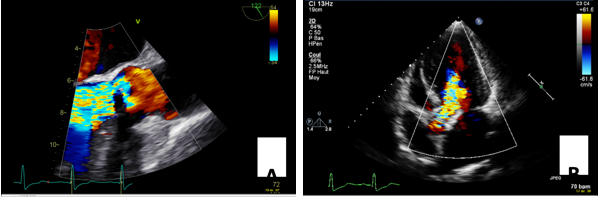

During the next four months, the catheter was flushed twice on a weekly basis and despite not infusing the patient with dialysate, about 1.85 liters of transudate ascites was drained every two days through the peritoneal catheter. Clinical examination showed large abdominal wall venous collaterals, no palpable nodes, muted cardiopulmonary auscultation, no abdominal pain nor lower limb edema at that time. Laboratory tests showed no sign of decompensated cirrhosis (serum albumin of 32 g/l (normal range: 40-49 g/l), Prothrombin time 75% (normal range: 70-100%), c-reactive protein 7mg/l (normal range: <10 mg/l), total bilirubin 1.0 mg/dl (normal range: < 1.2 mg/dl). A liver magnetic resonance imaging and CT scan ( Figure 1) revealed perihepatic ascites, central fibrosis, and preserved permeability of the supra-hepatic veins but signs of chronic obstruction of the portal vein.

Figure 1.Abdominal computed tomography revealing perihepatic and abdominal ascites. The peritoneal dialysis catheter is still in place.